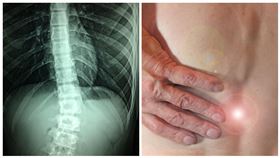

「3地雷姿勢」超傷脊椎!你中幾項?

脊椎是人體中軸,當身體傾斜或彎曲的角度愈大,脊椎便會...